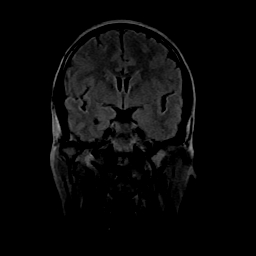

女性,47岁。mri号03027,外伤致头痛9天,抽搐一天,原无类似病史。

双侧海马的信号都有异常。

双侧海马硬化!

颞叶前部萎缩,海马萎缩,t2wi海马高信号,支持海马硬化。

双侧海马硬化.

双侧海马区t1低,t2高信号。为什么都考虑硬化?发病原因?鉴别诊断:炎症,梗塞等能一下子除外吗?